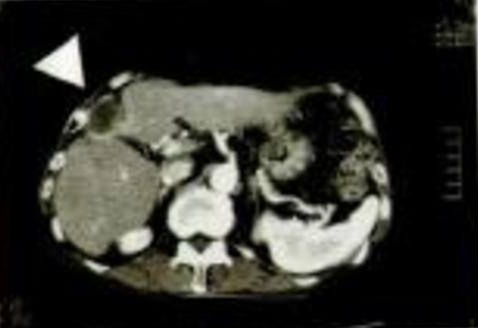

Imaginea CT stânga aparține unui pacient de sex masculin, în

vârstă de 81 ani, suferind de carcinom hepatocelular.

La stânga sus, porțiunea mai întunecată (simbolul ) decât perimetrul adiacent reprezintă zona afectată de cancer. Mărimea este considerabilă, de 102 mm x 44 mm, stadiul clinic fiind 4 (starea cea mai avansată).

Vârsta și stadiul bolii au determinat renunțarea la tratament, a luat însă parte la un studiu referitor la eficacitatea Oyama Agaricus, cu inițierea ingerării ciupercii menționate.